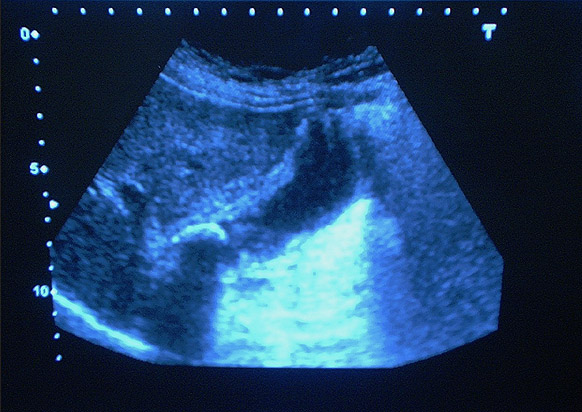

Quiste sinovial muñeca. Eco.